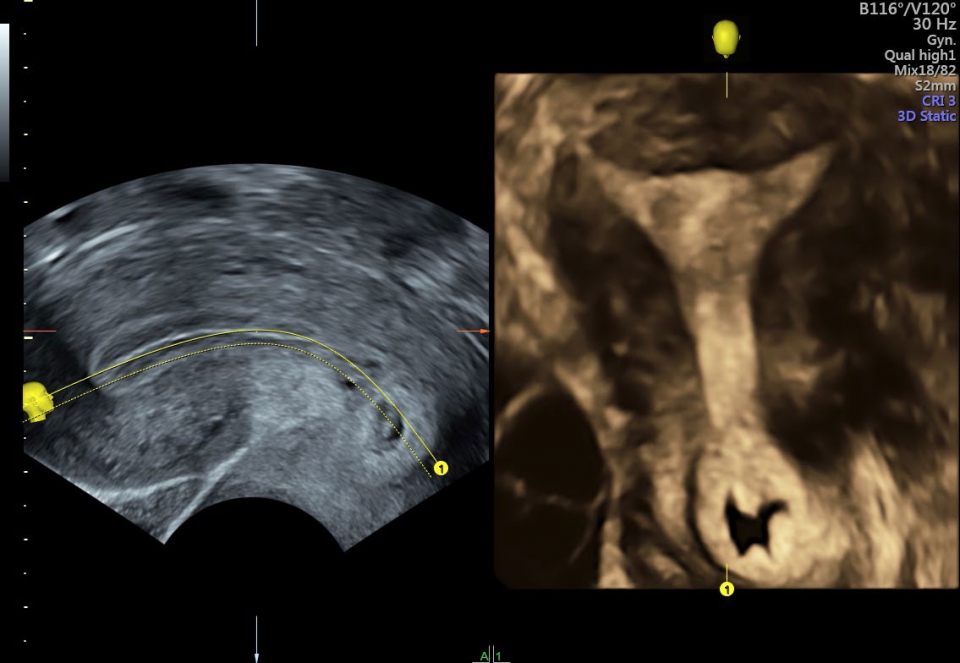

УЗИ аппарат Voluson S10 позволяет проводить обследования высочайшего уровня с максимальной точностью диагностики. Благодаря технологии Voluson Core Architecture достигнут высокий уровень качества изображений с возможностью последующей обработки и анализа даже после проведения скрининга. Технология HDlive делает изображения удивительно реалистичными и объемными.

• SonoRenderlive (Автоматическое объемное изображение): Эта функция упрощает получение объемного изображения путем автоматического выбора положения плоскости визуализации для 3D- и 4D-режимов. Это сокращает необходимость вручную настраивать параметры и упрощает процесс получения объемных изображений.

• SonoAVC (Автоматический расчет объема): Эта функция позволяет визуализировать и рассчитывать размеры и объем гипоэхогенных образований, таких как фолликулы яичника или структуры головного мозга плода. Она помогает в оценке этих образований и отслеживании их изменений в течение времени.